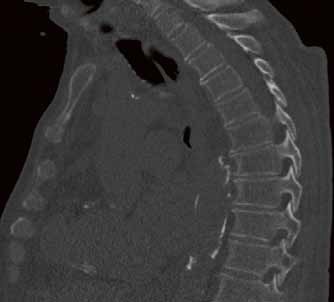

Die Klinik verfügt über 14 Computertomographen (CT), zwölf Magnetresonanztomographen (MRT) sowie zahlreiche Ultraschallgeräte. Allein am Campus Benjamin Franklin führen die Radiologen an sieben Tagen die Woche je zwischen 50 und 60 CT Untersuchungen täglich durch. Seit knapp drei Monaten steht ihnen dazu der neue 160-Schicht-Low-Dose-CT Aquilion PRIME zur Verfügung. Ein weiterer Aquilion PRIME sowie ein 640-Schicht-Volumen-CT Aquilion ONE ViSION EDITION wurden am Campus Mitte installiert. „Als wir nach einem neuen CT gesucht haben, war klar, dass dessen Ausstattung allen universitären diagnostischen Anforderungen gerecht werden muss", erklärt Dr. Stefan Niehues, Radiologe und Oberarzt der Klinik für Radiologie am Campus Benjamin Franklin.

„Mit dem neuen CT Aquilion PRIME können wir das komplette radiologische Spektrum der Charité abdecken. „Die gesamte Polytrauma-Diagnostik über die Akutversorgung bis hin zur Neuroradiologie und Diagnostik bei jungen Menschen führen wir mit dem Aquilion PRIME durch."

Dass sich Dr. Niehues und sein Team in einem langen und aufwendigen Entscheidungsprozess für das innovative CT aus dem Hause Toshiba ausgesprochen haben, hat mehrere Gründe. „Ich war Sofort beeindruckt von der Rechnergeschwindigkeit", sagt Dr. Niehues. Die Rekonstruktion der Bilder erfolge am Aquilion PRIME in einem Bruchteil der Zeit, die früher vergangen sei, bis das CT die komplette Bildserie samt Rekonstruktionen erstellte. „Heute haben wir alle Bilder nach wenigen Minuten", weiß Dr. Niehues, er hat das Intervall zwischen Untersuchung, Scan und Rekonstruktion aus Interesse selbst gestoppt. Früher sei das Polytrauma-Team samt Patient dann oft schon längst wieder verschwunden gewesen. „Die ständige Entscheidung zwischen schneller Rekonstruktion und einer kompletten Serie in dünnen Schichten und guter Bildqualität fand ich belastend - mit dem Aquilion PRIME hat sich das Problem gelöst", resümiert Dr. Niehues.

Neben der Rechnergeschwindigkeit lautet das Schlüsselwort bei dem neuen Gerät „Adaptive Iterative Dosis-Reduktion (AIDR 3D)". „Dieser mathematische Algorithmus erlaubt es uns, mit einem Bruchteil der Dosis zu arbeiten, die wir bisher für die erforderliche Bildqualität benötigt haben", weiß der Radiologe.

„Durch die Spitzentechnologie können wir bei gleich hoher Bildqualität die Dosis an Röntgenstrahlung bei vielen Untersuchungen auf ein Drittel reduzieren."